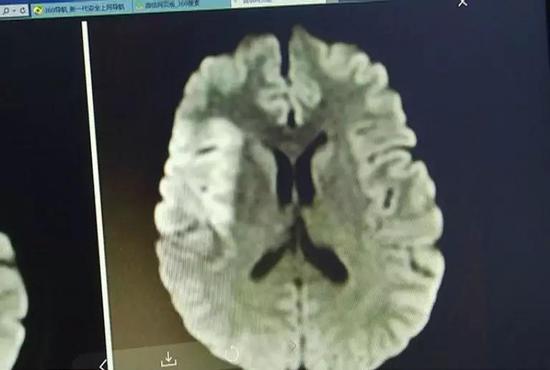

当时阿兰的脑部状况已经十分严重

医生为她取出了2公分的血栓

这是一般患者的2倍!